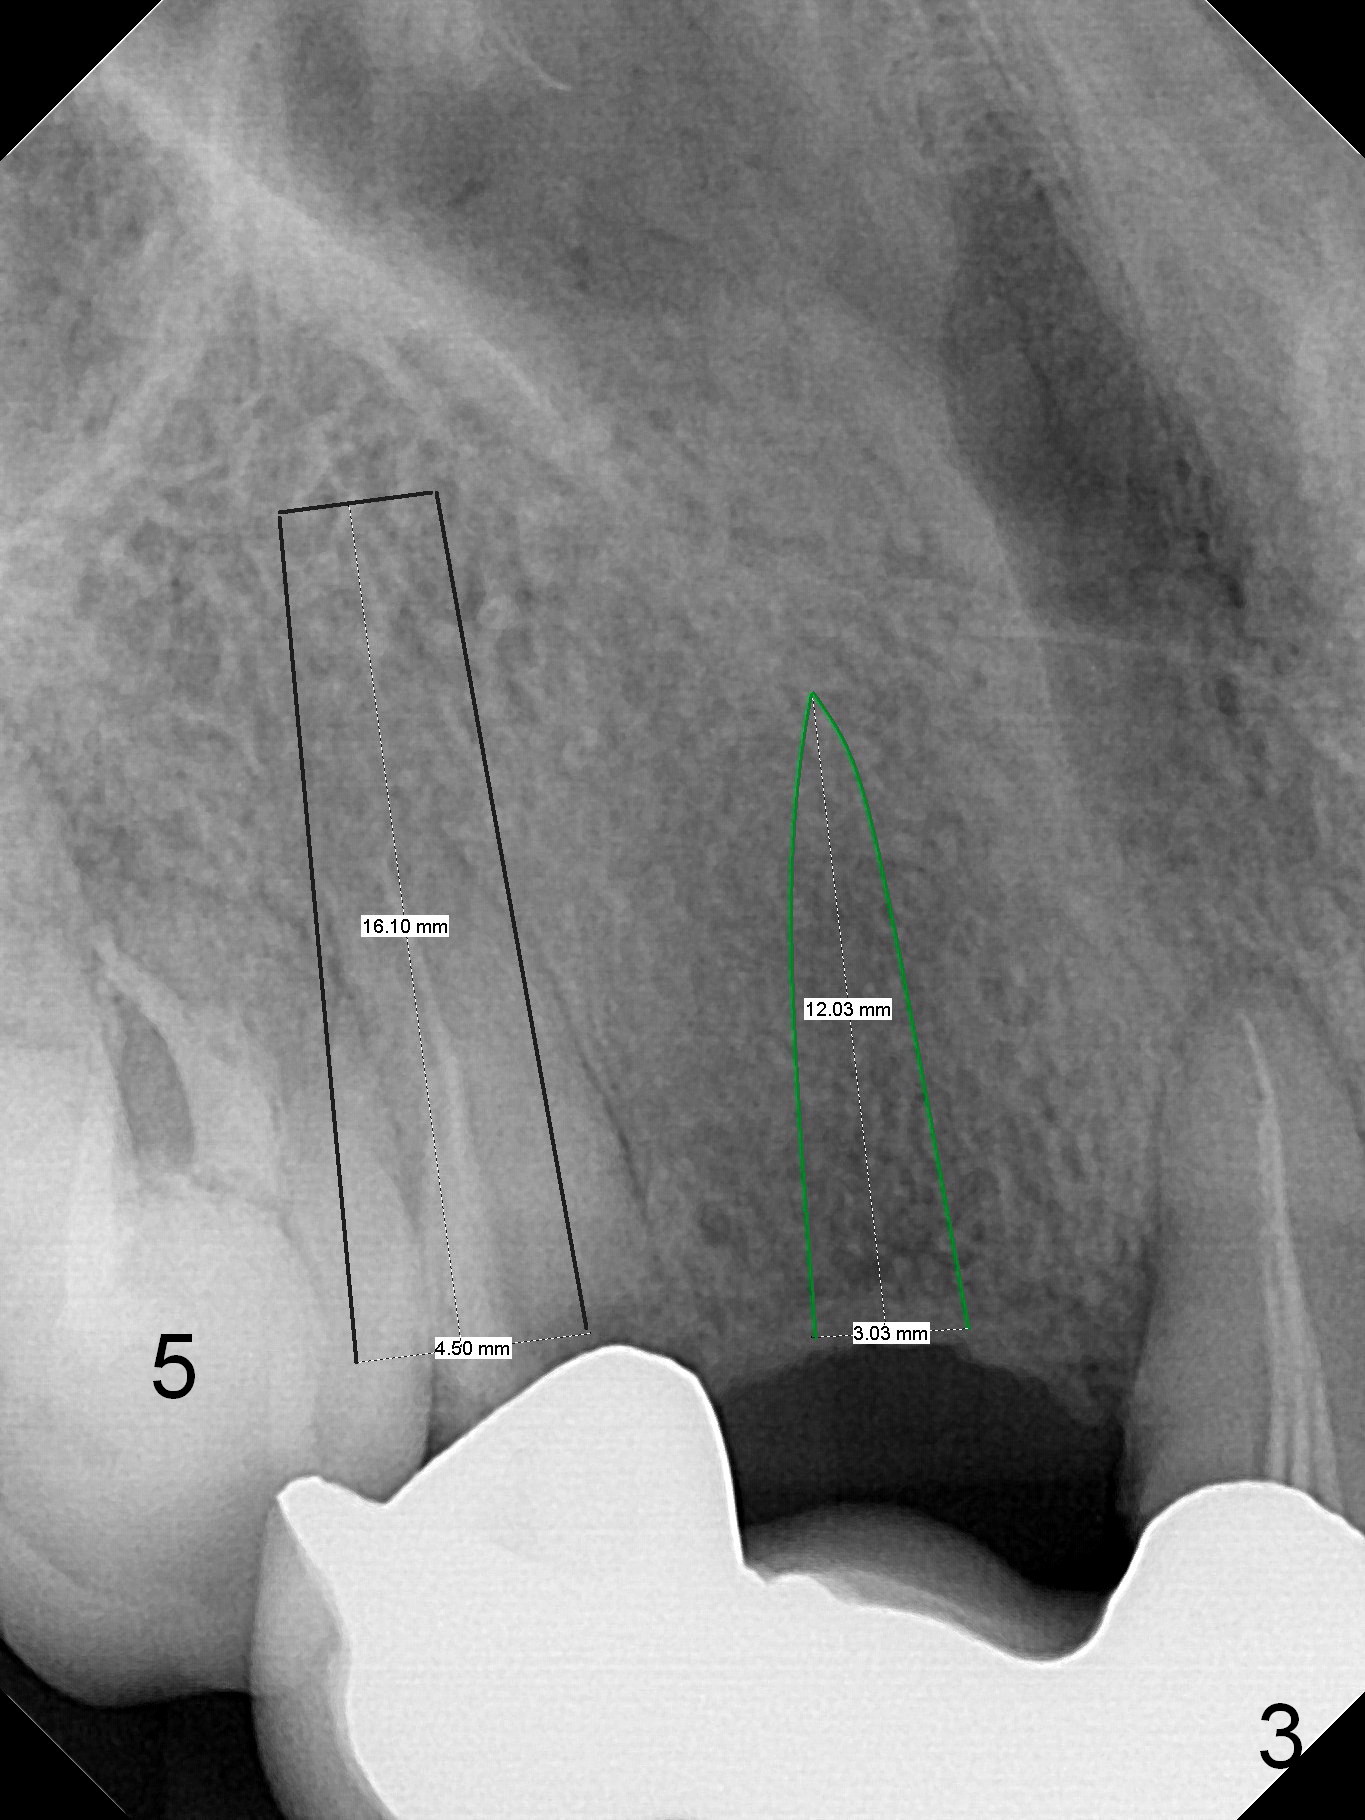

A 43-year-old woman has poor dentition including the tooth #5 (Fig.1) for RCT (Fig.3) and the teeth #2, 30 and 31 are missing.  The retainer at #6 fractures (Fig.1 *).  After sectioning the bridge between #7 and 8, fabricate prefabricated post at #6 if the latter is salvageable.  Otherwise extract (Clindamycin) and implant (Fig.3).  Anyway, a 3-mm or smaller one-piece implant is to be placed at #7 for stability and retention.  Pay attention to the labial concavity at #7 (Fig.2 *).  Surgical stent has been made.